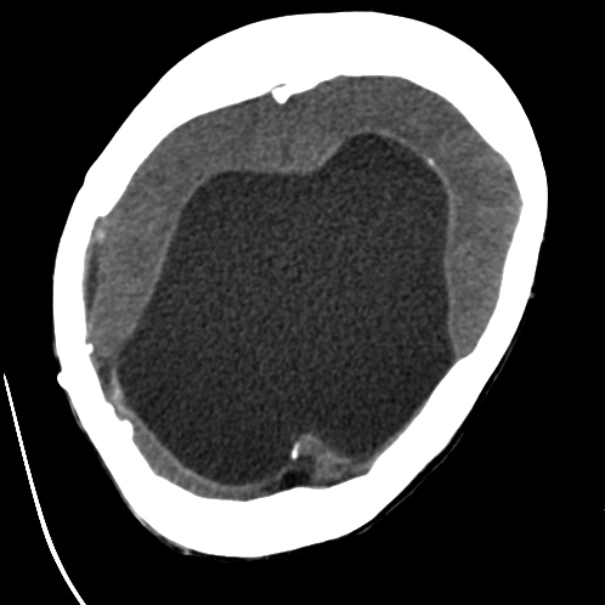

Não úng thủy tắc nghẽn ở não thất (Obstructive Hydrocephalus)

16/03/2026